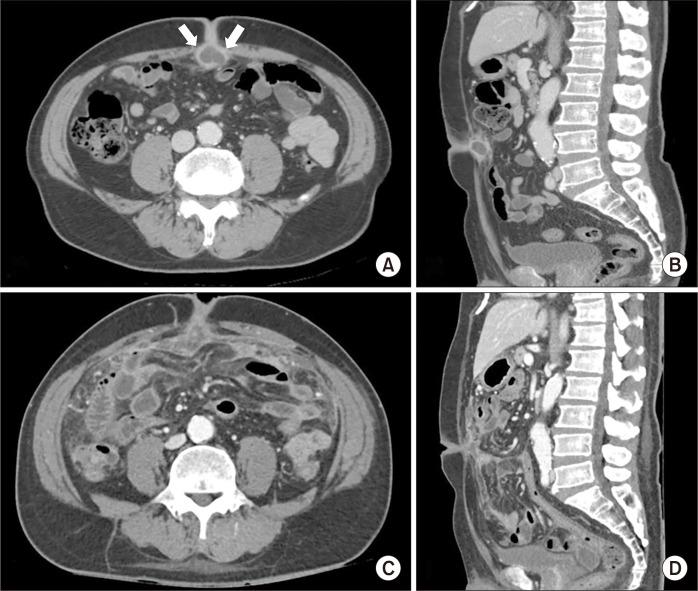

Omphalitis is an infection of the umbilicus that can cause inflammation to spread. Omphalitis is rare in adults; however, it can occasionally occur owing to urachal remnants. A 61-year-old male patient with abdominal pain and umbilical pus was admitted to the emergency room. Abdominal computed tomography revealed peritonitis with multiple intra-abdominal abscesses. The patient was diagnosed with peritonitis resulting from urachal cyst rupture. Laparoscopic drainage of the abscesses and excising of the umbilicus and intra-abdominal fistula tract were performed. Antibiotics were administered, and the patient was discharged uneventfully. The rarity of peritonitis caused by infection and urachal cyst rupture can make diagnosing omphalitis challenging. Therefore, in this case report and literature review, we discuss the diagnosis and treatment of complicated omphalitis, which rarely progresses to peritonitis owing to ruptured urachal cysts.

脐炎是一种可导致炎症扩散的脐部感染。脐炎在成人中较为罕见;然而,它偶尔可因脐尿管残余而发生。一名61岁男性患者因腹痛和脐部有脓液被送入急诊室。腹部计算机断层扫描显示腹膜炎伴多发腹腔内脓肿。该患者被诊断为脐尿管囊肿破裂导致的腹膜炎。进行了脓肿的腹腔镜引流以及脐部和腹腔内瘘管的切除。给予了抗生素治疗,患者顺利出院。由感染和脐尿管囊肿破裂引起的腹膜炎较为罕见,这可能使脐炎的诊断具有挑战性。因此,在本病例报告和文献综述中,我们讨论了复杂脐炎的诊断和治疗,这种脐炎很少因脐尿管囊肿破裂而进展为腹膜炎。